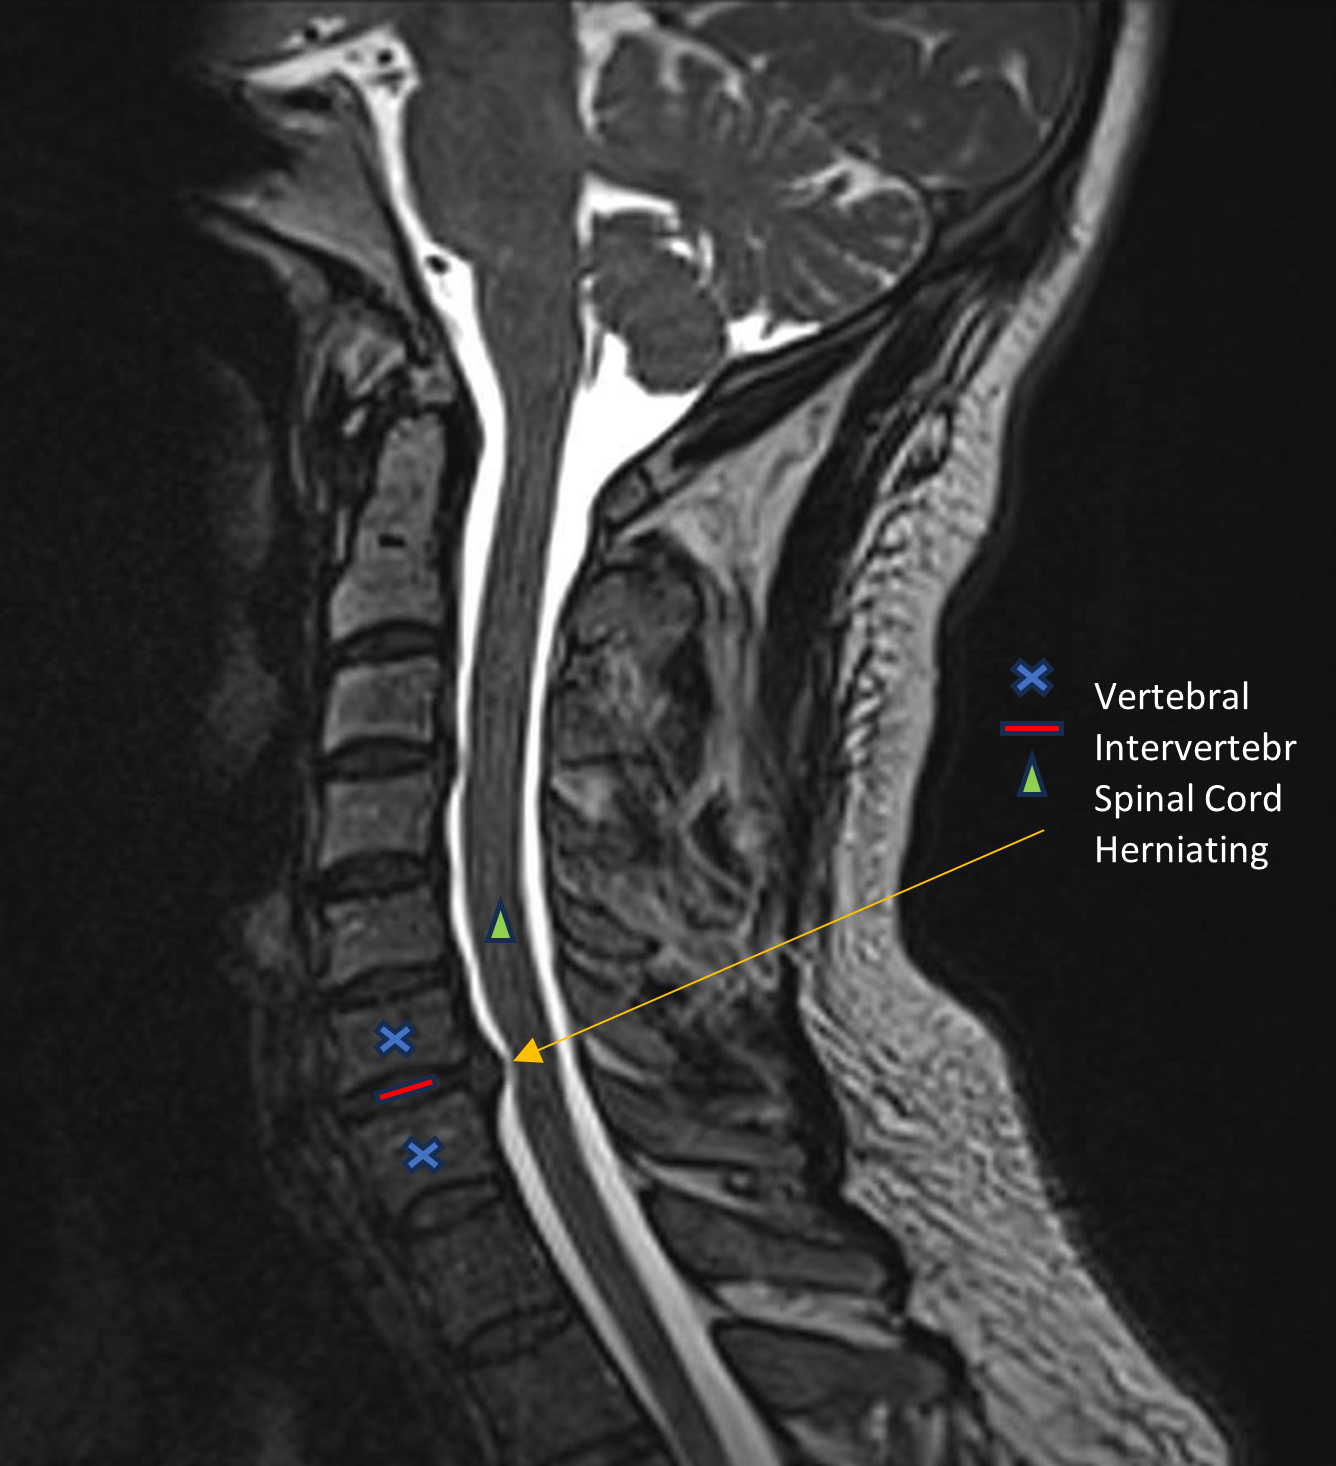

Magnetic resonance imaging (MRI) scans. MRI scans create better images of the body's soft tissues, such as muscle, fat, blood vessels, nerves, and fluids. An MRI of the neck can show if your nerve compression is caused by damage to soft tissues — such as a bulging or herniated disk. It can also help your doctor determine whether there is any damage to your spinal cord or nerve roots.

MRI of bulging disks in spine

This MRI image shows bulging disks pressing on the spinal cord.